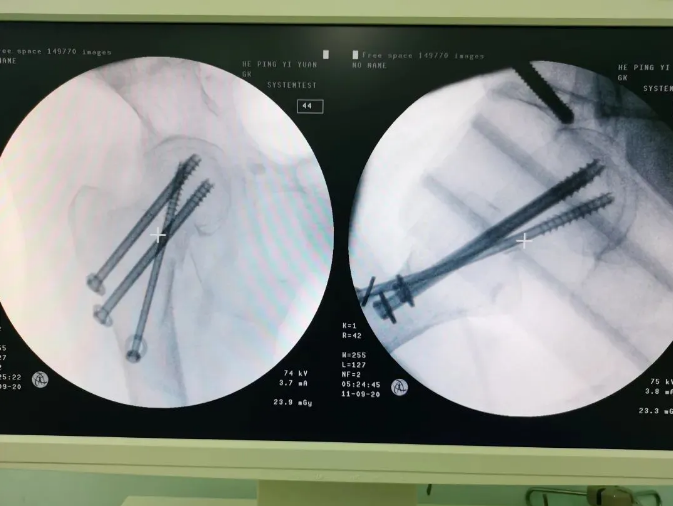

規(guī)劃入路

天璣機(jī)器人置入螺釘

螺釘置入后